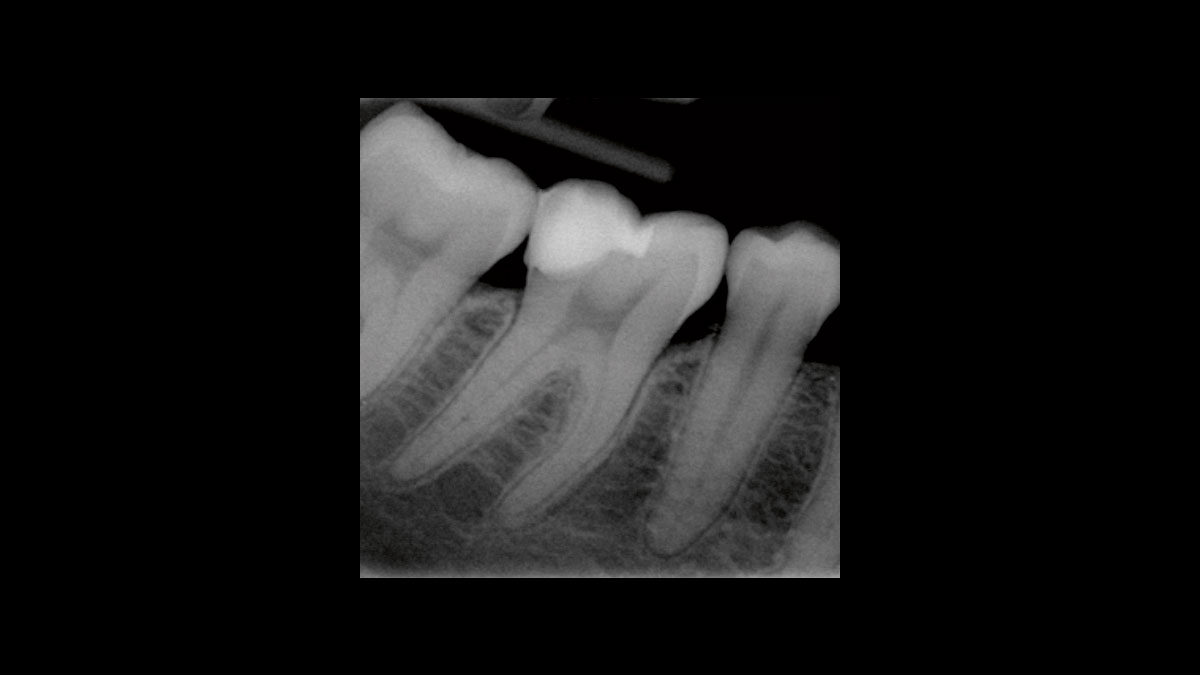

Эндодонтия

На видео и изображениях представлены следующие варианты применения:

• Подавление микробной контаминации в эндодонтии

• Подавление микробной контаминации при омертвении

Подавление микробной контаминации в эндодонтии